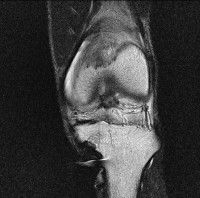

무릎 mri 간단히 봐주실 수 있으시나요 ㅠㅠ

안녕하세요 8년전 십자인대 수술하고 최근 무리한 운동에 무릎 불편감이 생겨서

mri 찍었습니다.

진단결과는 첫 찍은 병원에서 활액막염 이라는 진단을 받았습니다. 혹시 봐주실 수 있으실까요?

올라온 MRI가 단편적이라서 정확한 진단에 어려움이 있지만 십자인대에는 큰 이상이 있지는 않은것 같으며, 무릎관절내 물이 있는 것으로 보아 활액막염의 진단이 맞을 것 같습니다.

하지만 단편적인 영상이기 때문에 촬영병원에서 정확한 판독지 등을 받으시는 것이 좋겠습니다.